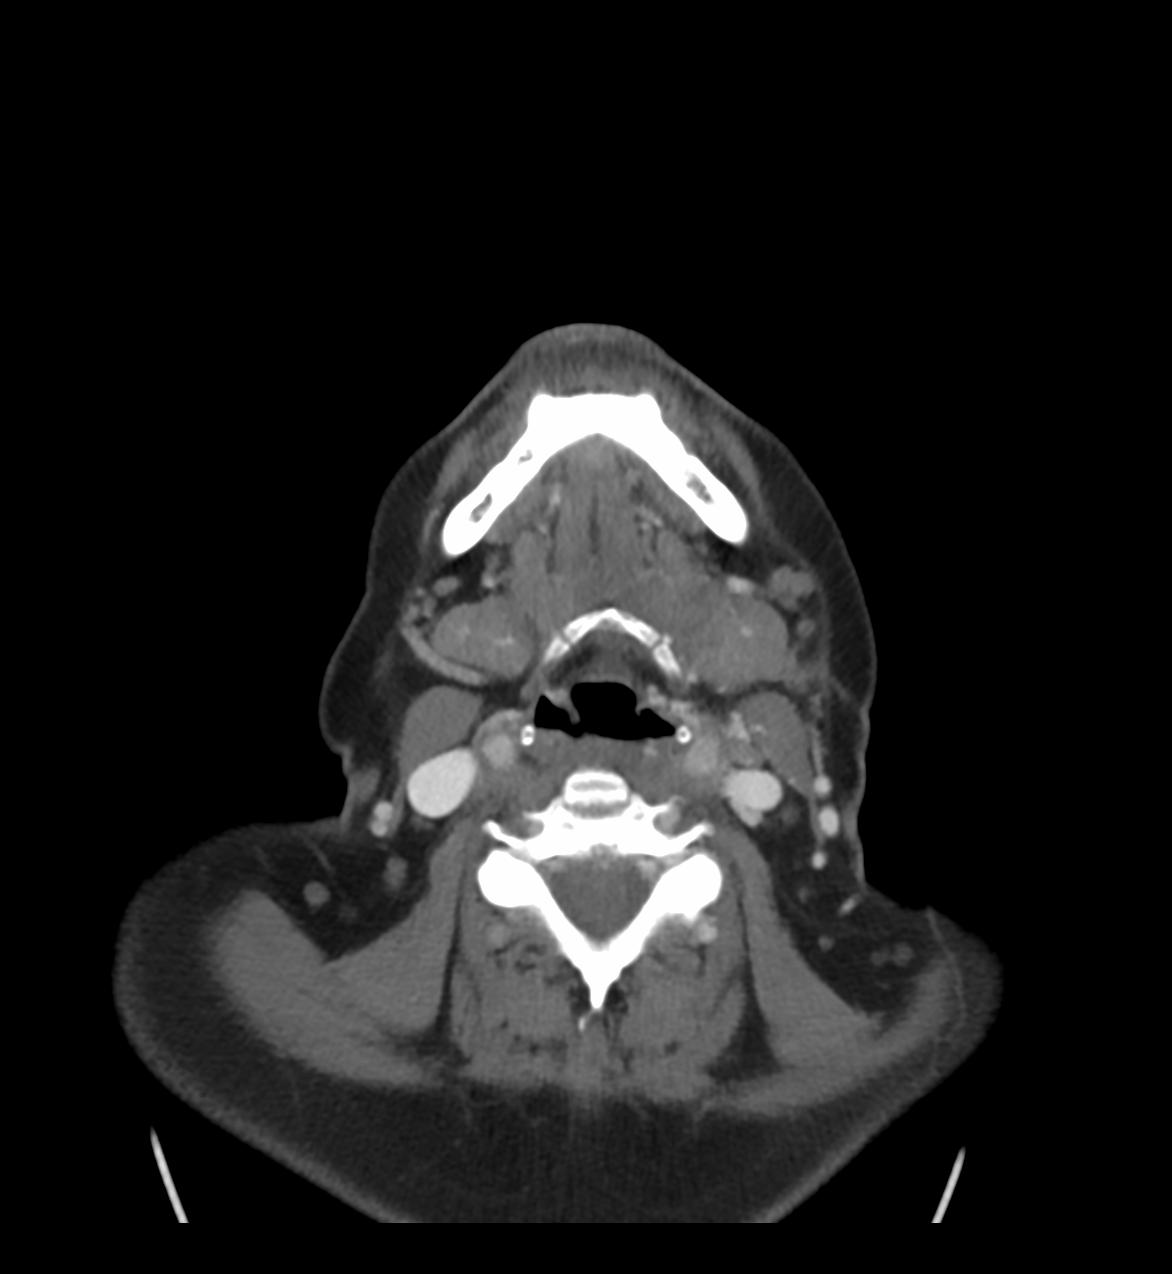

(Darstellung des Hirnschädels, Mittelgesicht, Nasennebenhöhlen und Felsenbeine)

Bei diesen Untersuchungen ist keine spezielle Vorbereitung notwendig. Je nach Fragestellung kann die intravenöse Gabe von Kontrastmittel erforderlich werden.

Die Untersuchungsdauer ohne Kontrastmittelgabe beträgt ca. 10 Minuten, mit Kontrastmittelgabe ca. 20 Minuten.